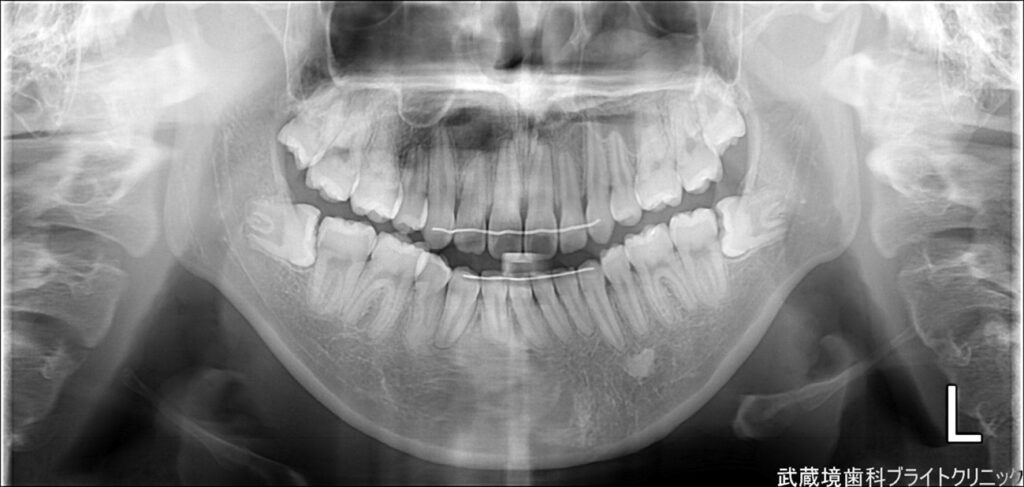

親知らずは抜いた方がいい場合が多いです。痛みがないからと放置しておくと、将来的に歯並びや噛み合わせに影響を与えたり、他の歯を圧迫したりすることがあります。

特に、親知らずが完全に生えない場合や、斜めに生えている場合は、早めに抜歯する方がリスクを避けられます。この記事では、親知らずを抜いた方がいい理由と、抜歯にかかる費用についても詳しく解説しますので、判断材料をしっかりとご確認いただけます。

親知らずが斜めに生えていたり、完全に生えなかったりすると、隣の歯を圧迫することがあります。これが長期的に続くと、歯並びや噛み合わせに影響を与え、矯正治療が無駄になったり、噛み合わせが不安定になることがあります。食事や会話に支障をきたすこともあるため、早めに抜歯することで将来的なトラブルを防ぐことができます。

親知らずが埋まっている場合

親知らずが完全に埋まっていると、歯茎の中で圧力がかかり、痛みや腫れを引き起こすことがあります。また、埋まった親知らずは歯科治療が難しく、感染症や膿が溜まるリスクがあります。放置しておくと、周囲の歯に悪影響を与えることがあるため、早期に抜歯することでトラブルを避けることができます。